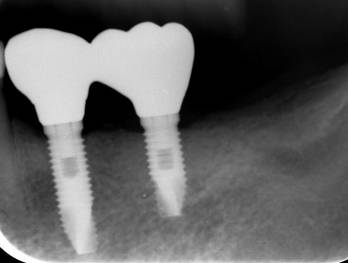

ストローマンインプラントとスプラインインプラント

術前

ストローマンインプラントとスプラインインプラントが隣り合わせに埋入されています.このころストローマンからスプラインに変えています。変えた理由は前歯部の審美性に優れていること、アバットメントの自由度があること、抜歯後すぐに埋入できるなどでした。

6年後。犬歯にコンポジット充填。第一大臼歯はメタルボンドになりました

8年後ほとんど変化がありません